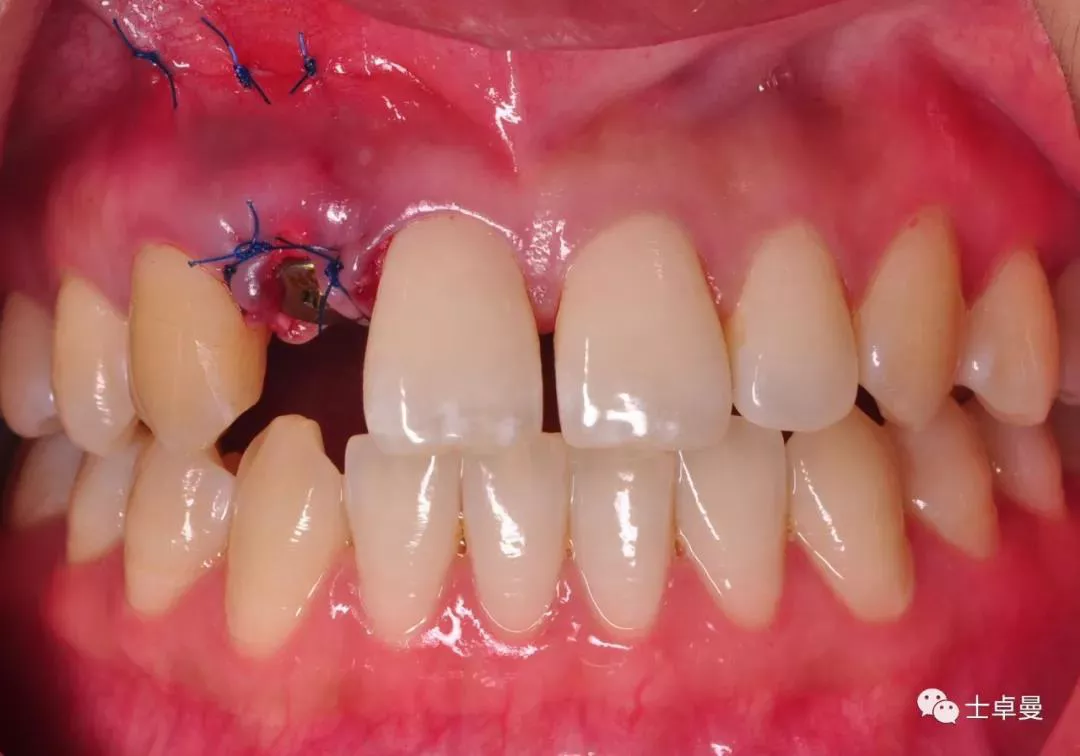

·       根尖穿孔区局部翻瓣,暴露穿孔部位;

根尖穿孔区翻瓣

·      放置骨粉、骨膜;

根尖区局部植骨

覆盖胶原膜

·       缝合;

缝合颌面观